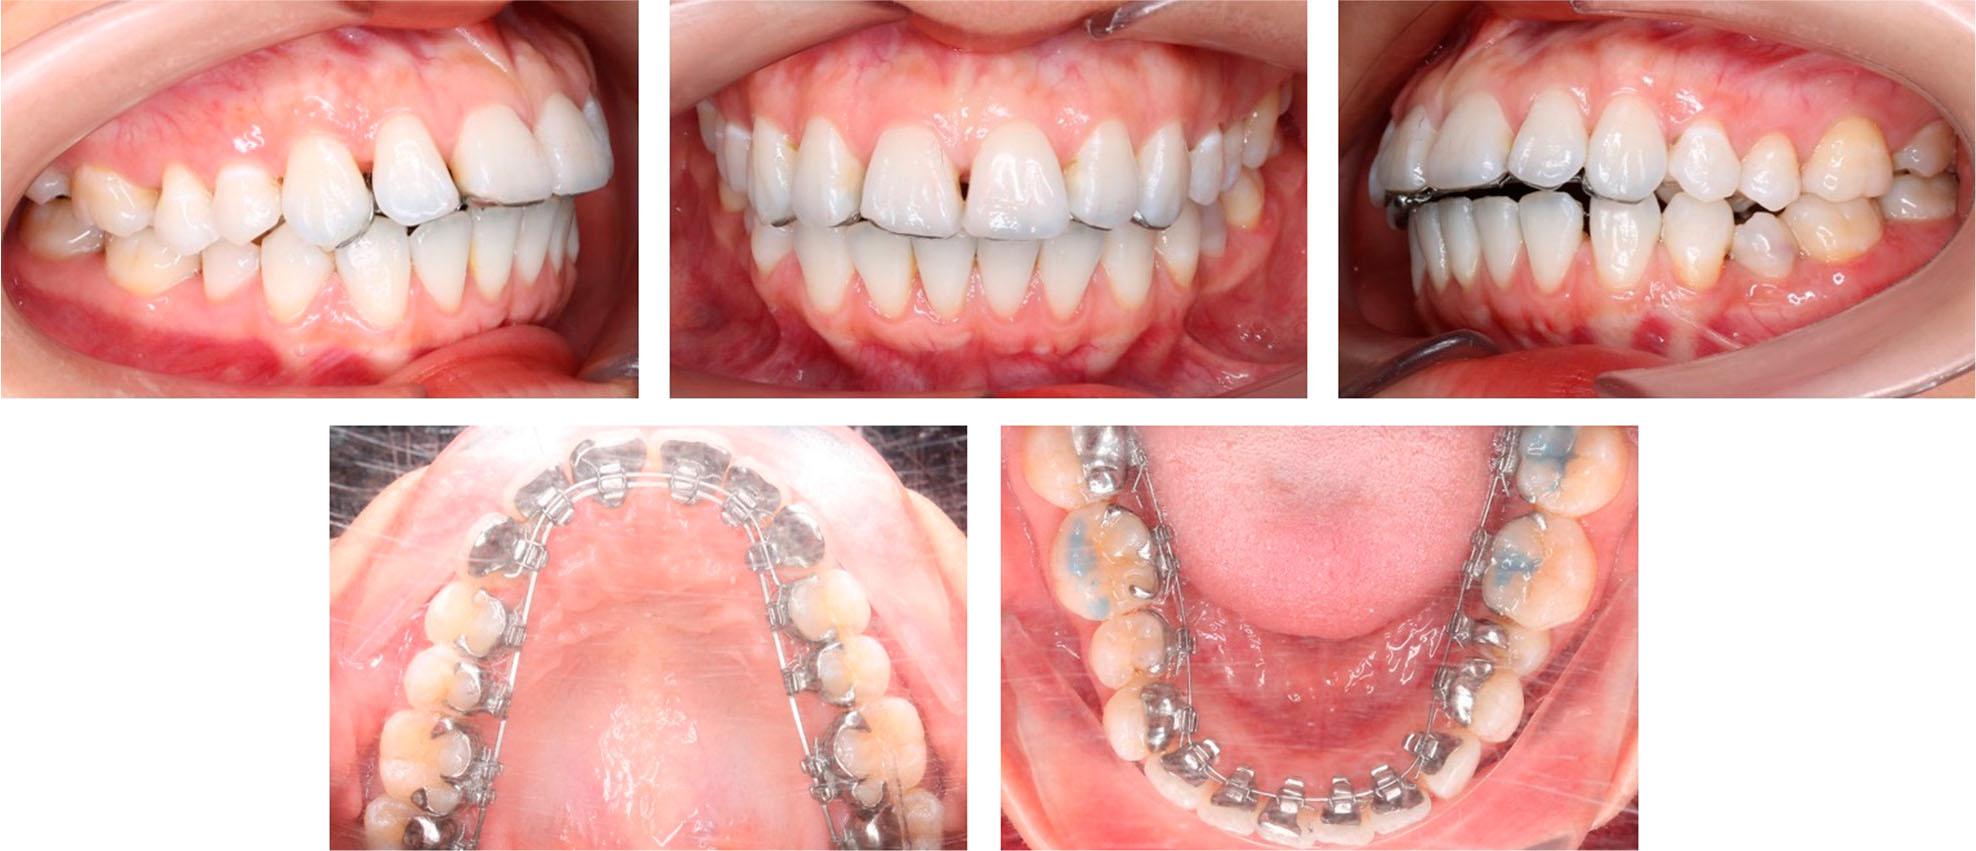

On intraoral examination, the patient had a mild Class III molar relationship on both sides, a mild Class III canine relationship on the right side, and a Class I canine relationship on the left side (Figure 2). The upper and lower arch forms were ovoid. There was moderate crowding in both arches with arch length discrepancies of 7.8 mm and 7.9 mm in the upper and lower arch, respectively. The maxillary and mandibular right central incisors were in an edge-to-edge relationship. The mandibular molars and second premolars were mesially inclined. The upper dental midline was co-incident with the facial midline, but the lower dental midline deviated 1.5 mm to the left.

Initially, the patient chose customised lingual appliances for the upper arch and labial stock ceramic brackets for the lower arch. However, the day following bonding, the patient requested the replacement of the ceramic brackets with customised lingual appliances in the lower arch to achieve maximum aesthetics and remove the prominence of her lower lip due to the bulk of the lower labial brackets.

Treatment commenced by bonding all teeth with 0.018” × 0.025” double-slotted customised lingual brackets except the mandibular right central incisor due to inadequate space. A dual-cured resin cement (RelyX U200, 3M Unitek, Monrovia, CA, USA) or a low-viscosity orthodontic adhesive (Enlight, Ormco, Glendora, CA, USA) combined with a universal primer (Single Bond Universal, 3M Unitek, Monrovia, CA, USA) may be used. The initial alignment and levelling were achieved using 0.012”, 0.014”, and 0.016” nickel-titanium round arch wires combined with open coil springs to open space for the mandibular right central incisor and left second premolar. Because of the flexibility of nickel-titanium arch wires, they were difficult to shape and so stock arch wires (Lingual straight wire, Ormco, Glendora, Calif) were selected from three standard arch forms at this initial period.12,13 The arch wire customisation is of minimal importance at this early stage because the nickel-titanium arch wires would not immediately express their arch form due to their flexibility. After gaining enough space, the mandibular right central incisor was bonded directly guided by the customised bracket base. The arch wire sequence was restarted from a 0.012” nickel-titanium round arch wire and progressed through stiffer arch wires.